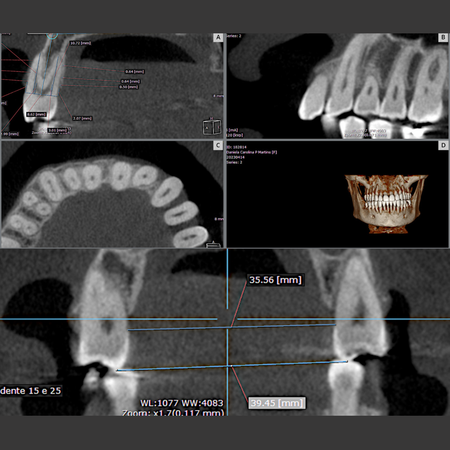

Objetivo: Avaliar as alterações, por meio de Tomografia Computadorizada de Feixe Cônico (TCFC), no osso alveolar vestibular e palatino de pré-molares superiores em indivíduos adultos jovens que foram submetidos à expansão dentoalveolar com alinhadores Invisalign ® e compará-las nos diferentes tipos faciais. Método: Quarenta e cinco pacientes (32 mulheres e 13 homens, média de 34,2 anos) realizaram expansão ortodôntica com alinhadores dentários. TCFCs foram realizadas antes (T0)...

Objective: This study aimed to evaluate changes, using Cone-Beam Computed Tomography (CBCT), in the buccal and palatal alveolar bone of maxillary premolars in young adult individuals who underwent dentoalveolar expansion with Invisalign® aligners, and to compare these changes across different facial types. Methods: Forty-five patients (32 women and 13 men; mean age: 34.2 years) underwent orthodontic expansion with clear aligners. CBCT scans were obtained before (T0) and after expansion of...